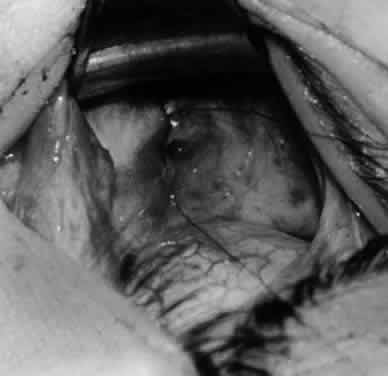

Fig. 10. The inferior oblique muscle is placed on the Green muscle hook. The exposed insertion is ready for myotomy, myectomy, disinsertion, placement of sutures for recession, or removal for the extirpation procedure.